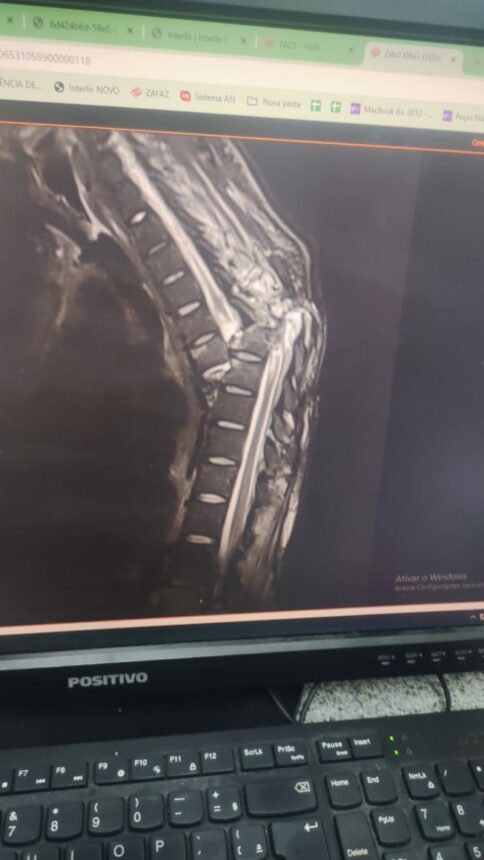

O Grupo Égia de Comunicação recebeu uma denúncia de que um jovem, 26 anos, aguarda há 50 dias por uma cirurgia. O homem teve fraturas na coluna e em quatro costelas, após capotamento no município de Alto Alegre.

Segundo informações da família, os médicos informaram que não há materiais para realizar a cirurgia. Alegaram ainda que fizeram o pedido dos utensílios, mas que a empresa responsável ainda não retornou.

A Secretaria de Saúde (Sesau) esclarece que, no momento, o paciente não pode passar por cirurgia devido a uma úlcera na região torácica, o que impossibilita a realização do procedimento.